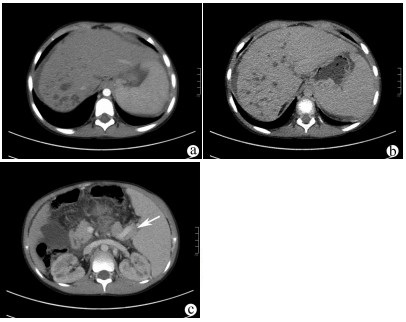

A case of type 2 diabetes with glycogenic hepatopathy

Renshu MA, Tong WU, Ge YU, Ying CONG, Guijie XIN

2021, 37(9): 2183-2184. DOI: 10.3969/j.issn.1001-5256.2021.09.035

Abstract(703) HTML (445) PDF (3125KB)(55)

Abstract: